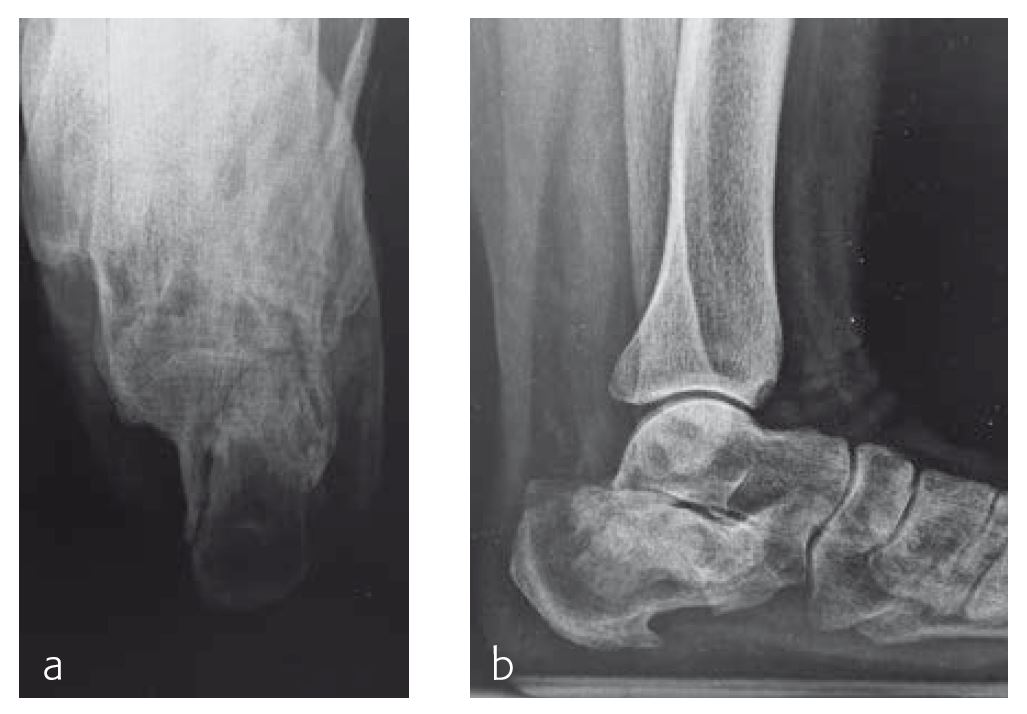

Case 2: 70-year-old patient

A 70-year-old female patient (Fig 1) had a long history of increasing painful deformity of her foot. She also noted increasing gait problems. There was no history of initial trauma. The examination showed severe rigid flatfoot deformity.

An extended triple arthrodesis was performed. Medially, the new Medial Column Plate was used, securing the talonavicular, naviculocuneiform, and tarsometatarsal joints (Fig 2). The X-plate is lateral and secured the calcaneo-cuboid joint. Two 7.3 mm screws were used to secure the subtalar joint.